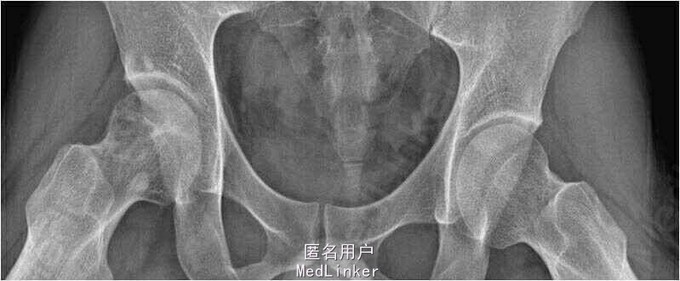

患者男,40岁,因”右髋关节疼痛半年余“入院。患者半年前无明显诱因出现右髋关节疼痛,后患者症状逐渐加重,余未见明显异常。

查体:右下肢关节关节间隙压痛,内旋、内收、外展、前屈活动受限,4字征(+),托马氏征内旋(+),撞击征(+)。X线平片提示右髋关节有骨赘形成。

诊断:右髋关节撞击综合征。行右髋关节镜检,关节腔清理及骨赘切除术。术后患者疼痛消失。